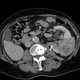

Congenital renal vein thrombosis